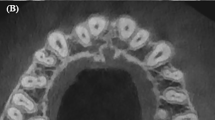

The present study was approved by the Institutional Review Board of the University of Medicine and Pharmacy at Ho Chi Minh City, Vietnam. The approval number of the study was 20,164-ĐHYD on 21st April 2020. All methods were carried out in accordance with relevant guidelines and regulations21. The study acquired intact extracted human molars obtained from many hospitals for numerous reasons, with informed consent obtained from all participants. With the data from a previous study1, the sample size was 302 root canals in 111 molars, according to calculations performed using statistical software (MedCalc Statistical Software version 19; MedCalc Software, Ostend, Belgium). The parameters for the Bland–Altman plot sample size window of the software were an alpha of 0.05, beta of 0.01, expected mean difference of 0.36, expected standard deviation of 0.31 and maximum allowed difference between methods of 1.1. The present study was performed following the method of a previous study19. Briefly, teeth were ultrasonically cleaned with an ultrasonic scaler (BobCat; Dentsply Sirona, Ballaigues, Switzerland). Teeth were thoroughly observed using a stereomicroscope to exclude defective teeth, such as those with an immature apex, external resorption, or a cracked root at a magnification of 10×. Teeth were coded with numbers on the coronal parts and were then placed in a plastic impression mould containing light silicone with a 3 mm wax layer on the floor. The plastic mould with teeth was then scanned using CBCT (Planmeca ProMax; Planmeca Oy, Helsinki, Finland) in endo mode, 90 kV, 10 mA, field of view 50 × 50 mm2 and a voxel size of 0.075 mm.

For the first part, the CBCT images were analysed using software from the CBCT manufacturer (Romexis Viewer; Planmeca Oy, Helsinki, Finland). From the slice thickness box of the software interface, different slice thicknesses were selected to measure the root canal length at three thicknesses, i.e., 0.6, 1.2 and 2.4 mm. The following steps were performed on the CBCT software.

In the bucco-lingual aspect, the clearest figure of the entire canal with the largest curved angle, from the orifice to the apex, was chosen by scanning every slice of the tooth at each slice thickness in the evaluation. The apical foramen (AF) was determined by the end of the canal, which was located at the root surface on the image, and the occlusal reference (OR) was located at the farthest and most occlusal position for the mesial canals or at the nearest and most occlusal position for the distal canals. A multisegmented line was then continuously traced from the AF to the OR (Fig. 1).

The root canal length measured by tools in the software was noted as the CBCT length (CL). The CBCT estimations were performed twice at two-week intervals to test the intra-examiner reliability.